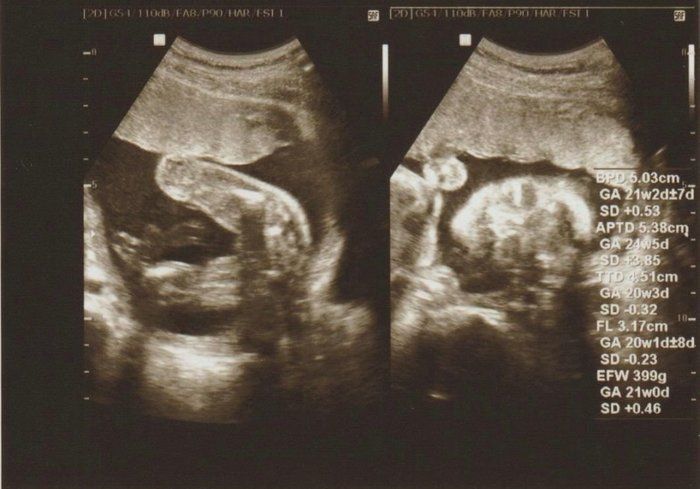

つぼいみきさんの妊娠20週目のエコー写真 胎動を感じ始める

推定体重400g 胎動を感じ始める

左写真には足2本が確認できます。この状態を見て先生に「確実に女の子でしょうね」と言われました。右は顔がうつっています。前回の検診の時よりさらにお顔がはっきりし、「輪郭はシャープだからパパ似かな?」と夫婦の会話も弾んでいました。胎動もポコッポコッと感じるようになり、パパも手をあてて胎動を感じることができ喜んでいました。前回の検診で私の体重が増えないことに悩んでいたはずが…この日の検診では1ヶ月で2.8kgも体重が増加。「一気に増えるのは良くないから少し気をつけようね」と先生から指摘を受けました。